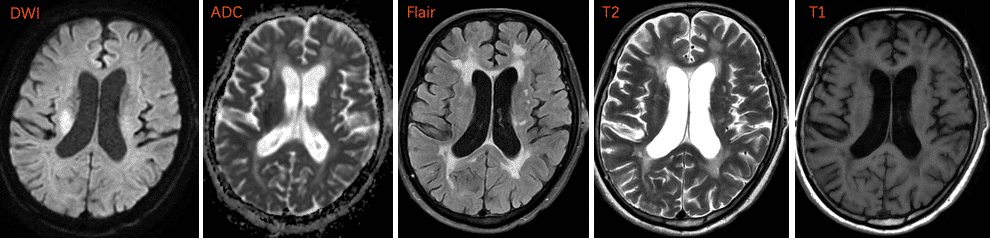

头DWI(2025-7-9 8:35 本院)序列见右侧侧脑室旁弥散信号异常,ADC序列相应部位呈低信号改变;Flair序列可见侧脑室前角、后角及基底节区可见片状缺血脱髓鞘改变,提示皮层下白质疏松;大脑皮层脑沟变深,侧脑室角变圆钝,符合老年性脑改变。